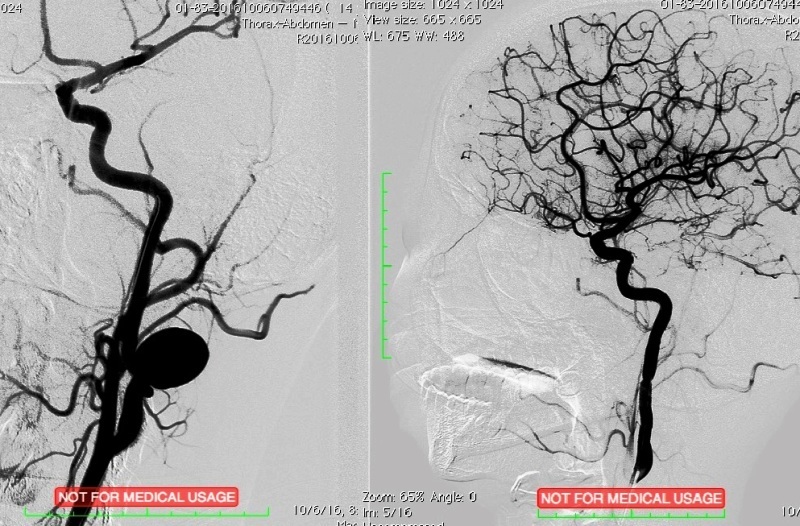

Trên phim chụp CT và chụp mạch máu xóa nền (DSA), khối phình lớn ở động mạch cảnh trong, vùng góc hàm, gần sàn sọ. Túi phình lớn gấp 5 lần kích thước trung bình của động mạch cảnh, nguy cơ vỡ rất cao.

E-kíp phẫu thuật đã tiến hành can thiệp nội mạch qua ống nội soi đi từ động mạch vùng đùi lên tiếp cận động mạch cảnh trong bên trái để đặt stent giá đỡ có màng, chặn đường cung cấp máu cho túi phình.

Sau phẫu thuật, phim chụp kiểm tra cho thấy không còn hình ảnh túi phình. Ca can thiệp đã thành công, hậu phẫu nhẹ nhàng và bệnh nhân được xuất viện ngay trong ngày hôm sau.